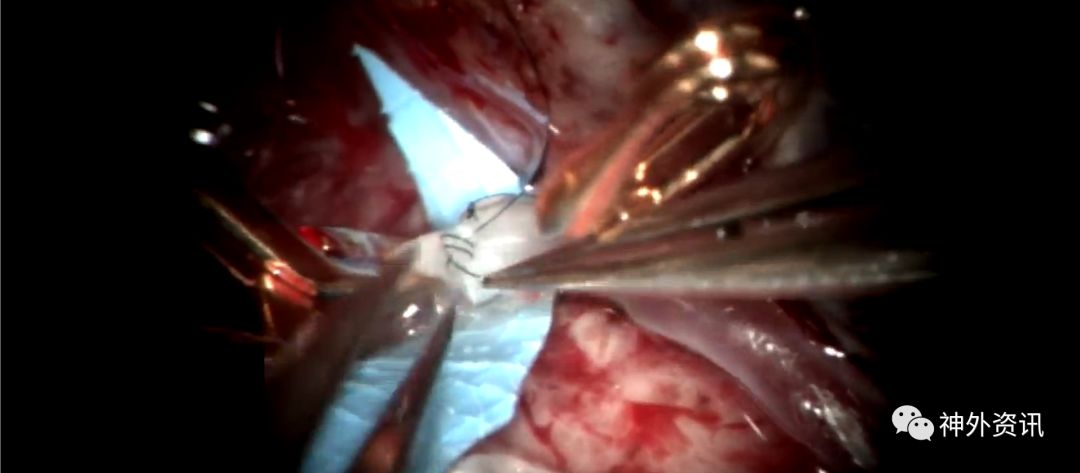

Michael T. Lawton,巴洛神经科学研究所(BNI)主席,精于各种脑血管疾病的治疗,已累及外科治疗4400余例颅内动脉瘤和700余例AVM,发表论文270余篇,参编书籍40余部,著有《Seven Aneurysms: Tenets and Techniques for Clipping》。